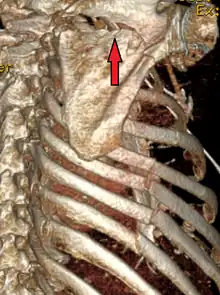

| A right sided scapula fracture with rib fractures underneath seen on a 3D reconstruction of a CT scan | |

Diagnosis

Most fractures of the scapula can be seen on a chest X-ray; however, they may be missed during examination of the film.[1] Serious associated injuries may distract from the scapular injury,[4] and diagnosis is often delayed.[3] Computed tomography may also be used.[1] Scapular fractures can be detected in the standard chest and shoulder radiographs that are given to patients who have had significant physical trauma, but much of the scapula is hidden by the ribs on standard chest X-rays.[4] Therefore, if scapular injury is suspected, more specific images of the scapular area can be taken.[4]